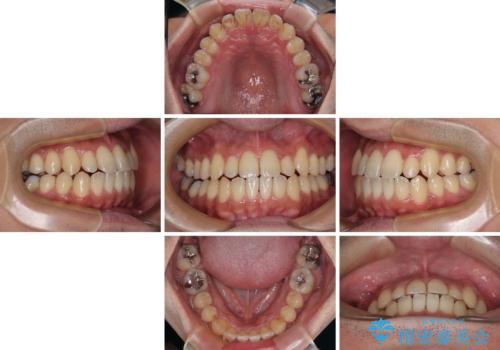

内側に引っ込んだ歯を治したい インビザラインの矯正治療

- 前歯のデコボコとクロスバイトを治したいとのことで来院された患者様です。

上下顎ともに歯列全体の側方拡大とIPR(歯と歯の間を削る)によってデコボコとクロスバイトが解消するように設計し、インビザラインにより治療を行うこととしました。

反対咬合特有の治療途中の前歯の干渉が長く続き、治療中に食事をとりにくく、ご迷惑をおかけしました。

前歯の咬み合わせの調整などを行い、安定した咬み合わせに仕上げることができました。